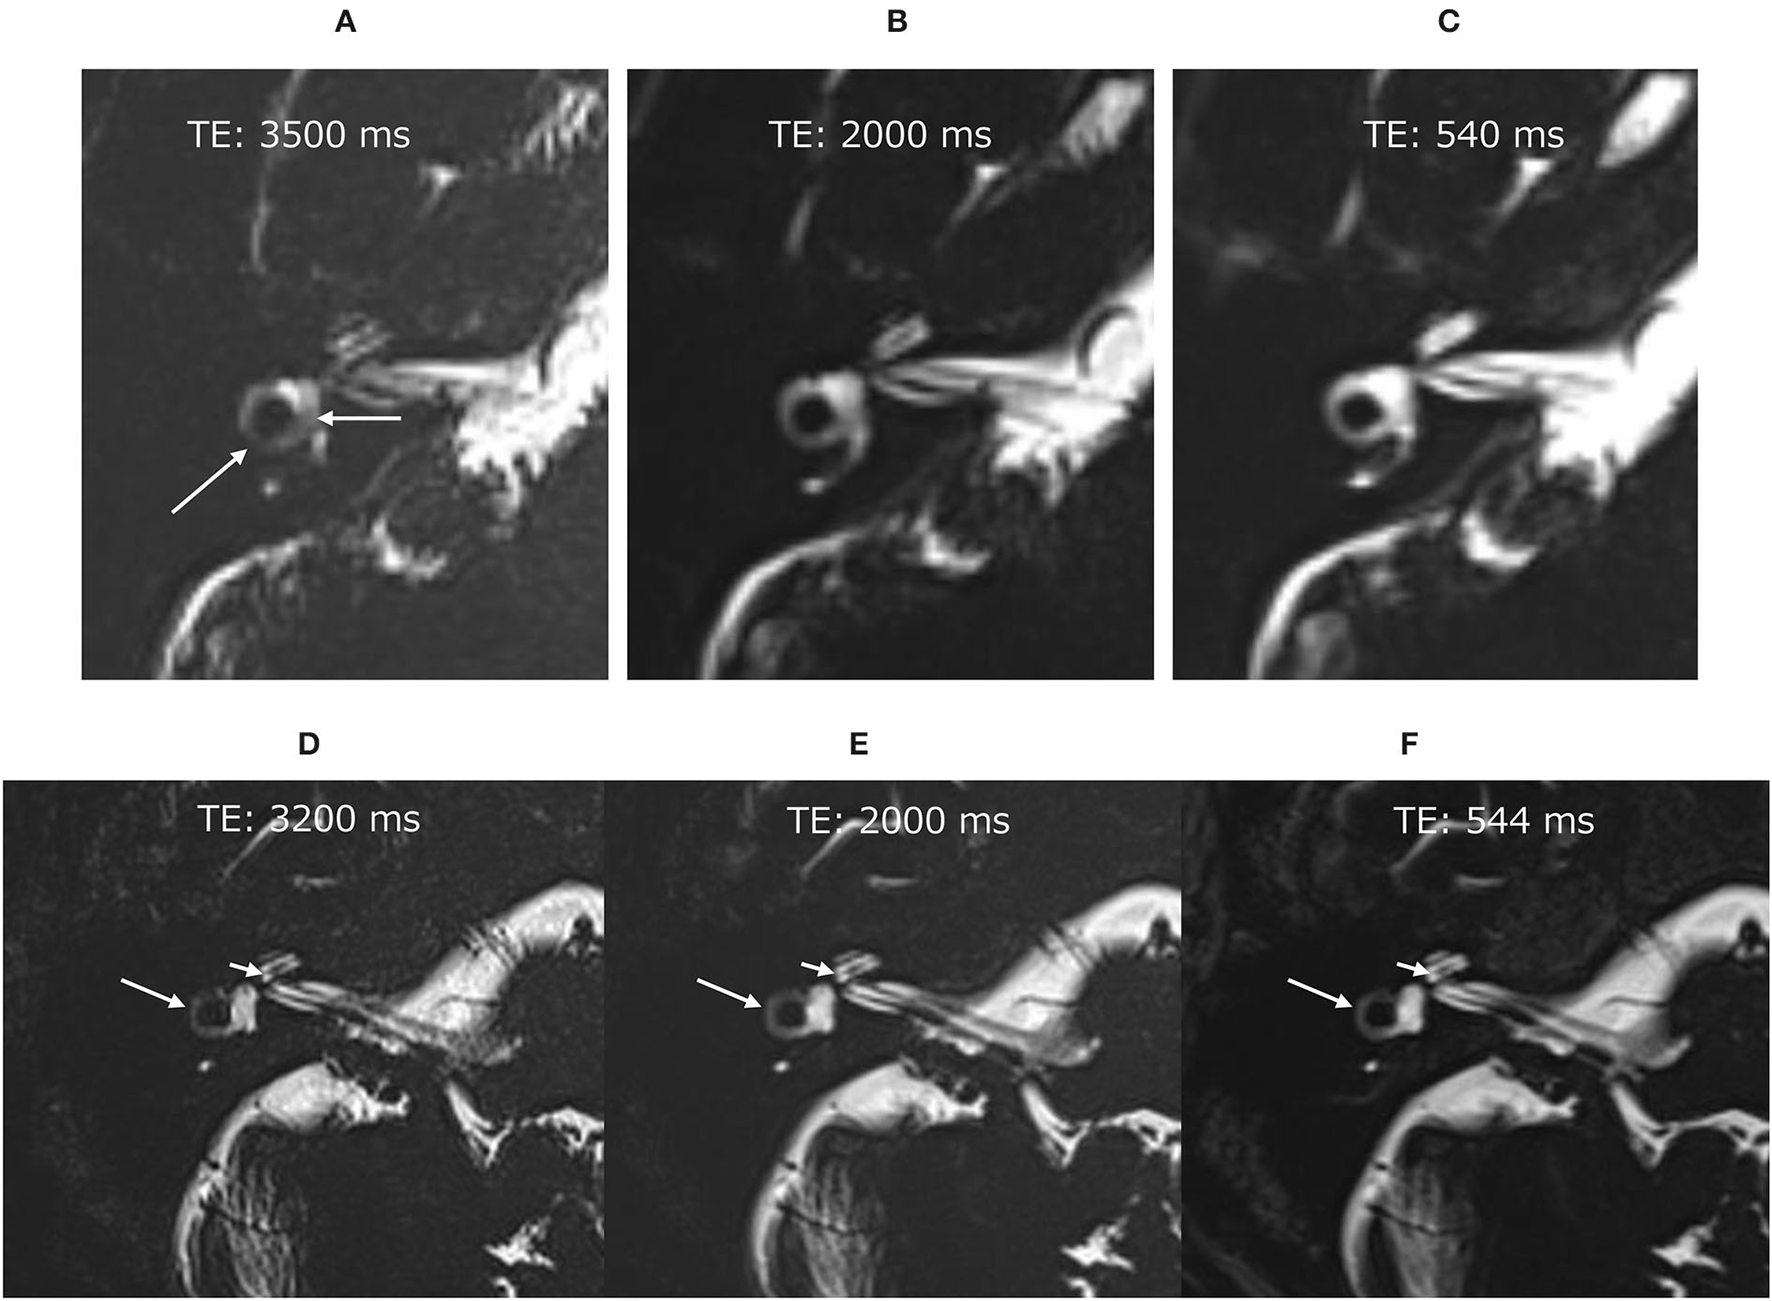

Phantom experiments and sequence optimization in human volunteers

In a pilot study, we performed phantom experiments to optimize the pulse sequence parameters for the scan after intratympanic administration of 17O-labeled saline. 17O-labeled water shortens the T2 time as an indirect effect in proton MRI (3). We prepared test tubes with various dilutions of 10 mol% 17O-labeled saline (Taiyo-Nissan Co. Ltd, Tokyo, Japan) as follows: original solution; dilutions of 2, 4, 8, 16, 32, 64, 128, 192, 256, 512, 1,024, 2,048, 4,096, 8,192, and 16,384 times; and normal saline. To visualize low concentrations of 17O-labeled water using T2-weighted images in the human inner ear with fine anatomy, we used hT2W MR cisternography and 3-D turbo spin–echo (SPACE: sampling perfection with application-optimized contrasts using different flip angle evolution) with TEs of 500–5,600 ms (16). In the phantom experiments, we could differentiate the 512 times dilution and normal saline using a TE of 3,500 ms (Figure 1). With an increasing TE, the signal–intensity ratio (SIR) (normal saline/512-times diluted 17O-labeled water) increased to 1.00 at a TE of 500 ms, 1.06 at a TE of 2,000 ms, 1.10 at a TE of 3,000 ms, and 1.12 at a TE of 3,500 ms. However, with an increasing TE, the image noise increased. We needed to identify the maximum TE value to visualize the fine inner ear anatomy with a reasonable scan time in humans.

A phantom experiment with test tubes of various 17O-saline concentrations. 10 mol% 17O-saline was diluted with normal saline. Numbers in the blue circles indicate the dilutions. The right lower corner tube (0%) indicates the tube filled with normal saline. Compared with normal saline, the slight signal decrease for 17O-saline was barely recognizable for the 512 times dilution for a TE of 3,500 ms (arrow), 128 times dilution for a TE of 2,000 ms (arrow), and 32 times dilution for a TE of 540 ms (arrow). Even at a TE of 540 ms, dilutions of <8 did not produce a visible signal.

Before the administration of 17O-labeled saline, we scanned three volunteers. The maximum TE to visualize the inner ear anatomy steadily in a reasonable scan time of 6 min was 3,200 ms (Figure 2). We could not predict the exact dilution ratio of 17O-labeled water saline in the perilymph nor how fast the 17O-labeled water or saline would permeate and distribute within the labyrinth. We decided to use three TEs to accommodate the various concentrations, 540, 2,000, and 3,200 ms, and to obtain images at multiple times. Using multiple TEs and images with various sensitivity to low concentrations of 17O-labeled water allowed us to perform image processing of the different TEs and to produce easily recognized images for the visualization of the 17O-labeled water distribution. All MRI scans were performed using a 3 T unit (Skyra, Siemens Healthineers, Erlangen, Germany) using a 32-channel array head coil. Details of the scan parameters are shown in Table 1.

Figure 2

Pilot scans in volunteers without administration of the 17O-labeled water tracer. In the image with an echo time (TE) of 3,500 ms (A), the vestibular signal was not uniform, and the lateral semicircular canal was not continuous (arrows). Note that these structures were visualized clearly in the images with a TE of 2,000 ms (B) and TE of 540 ms (C). Pilot scans in another volunteer without 17O-labeled water tracer administration. Although the image with a TE of 3,200 ms was slightly noisy (D), the anatomy of the labyrinth could be seen clearly. The signal for the vestibule was more uniform in the image with a TE of 3,200 ms (D) than in that with a TE of 3,500 ms (A). For example, the osseous spiral lamina of the cochlea (short arrow) and the lateral semicircular canal (arrow) could be identified in all images of this volunteer (D–F).